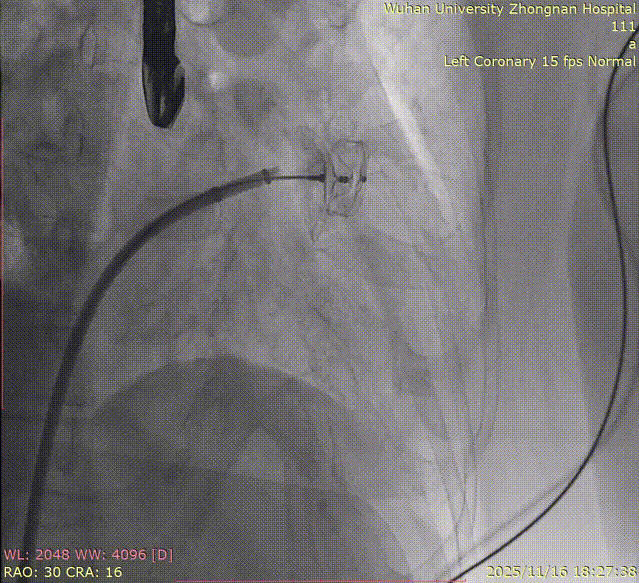

K-Clip® Tricuspid Annuloplasty (Seamless Transition):Immediately after LAAC, the operators established a new vascular access route and advanced the K-Clip® delivery system directly into the right atrium, targeting the posterior-septal and anterior-posterior commissures of the tricuspid annulus. Under real-time ultrasound guidance, the team precisely anchored, clipped, and released the devices.

6.Repeating the process for the second clip: steering, rotating, targeting, and engaging the anchor screw.

7.Opening arms, adjusting orientation, landing, and closing the second clip.

8.Right coronary angiography confirming no impact on the RCA before releasing the second implant.